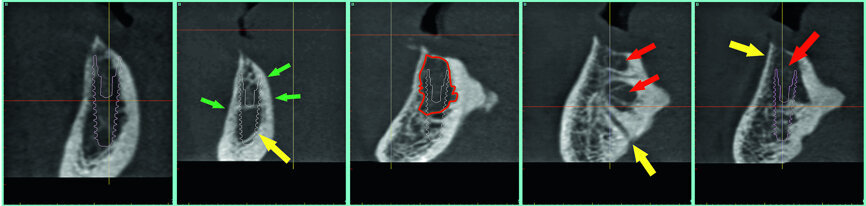

Contrary to the 2-D view of the panoramic radiograph, 3-D imaging and interactive treatment planning software allows clinicians to truly understand the patient's existing anatomy. For the example of the fully edentulous mandible, the CBCT scan revealed that the underlying bony ridge was quite sharp and uneven at the crest. This presentation would certainly not be favourable to place implants with a flapless surgical approach. In fact, to facilitate the placement of implants, and facilitate the restorative phase, it would be beneficial to flatten the irregular ridge to gain the appropriate and desired width at the alveolar crest (Fig. 8).

The cross-sectional images revealed the presence of a thick facial buccal plate of bone in some areas, thinner in others, and a thick lingual plate of bone generally. The surprise was in the symphysis, a hollow area in the anterior central area exactly where implants would be placed! Other hollow areas and intraosseous vessels were noted (see arrows, Fig. 10). The ‘hollow’ areas in the anterior symphysis are as illustrated in the 3-D reconstructed volumes with four simulated implants in an occlusal view.

The hollows in the anterior symphysis area of the mandible are seen in a ‘clipping’ view with simulated implants, slicing through the 3-D volumetric reconstruction (Figs. 11a & b). This anatomical variation could not be determined with 2-D imaging modalities. Once this was known, the planning of implants could proceed with the knowledge of the individual patient’s anatomical presentation. The patient was informed of the issues related to the anatomy as shown on the 3-D simulation from the CBCT scan. These images are invaluable to educate the patient and improve case acceptance, and extremely invaluable for the diagnostic process in determining the best surgical approach. Proper diagnosis and treatment planning through 3-D imaging and simulation software revealed that the narrow ridge would have been a significant obstacle using a flapless approach, and the hollows in the bone may have caused significant issues in the placement and the ability to stabilise the four implants that were eventually placed.

Based on the CBCT data and interactive treatment planning simulations, it was elected to complete the surgical placement of four implants in the anterior symphysis in a ‘diagnostic-freehand’ manner. The anatomical landmarks were clear and allowed the accuracy of implant positioning. The knife-edged ridge required a full flap surgical approach (Fig. 13).